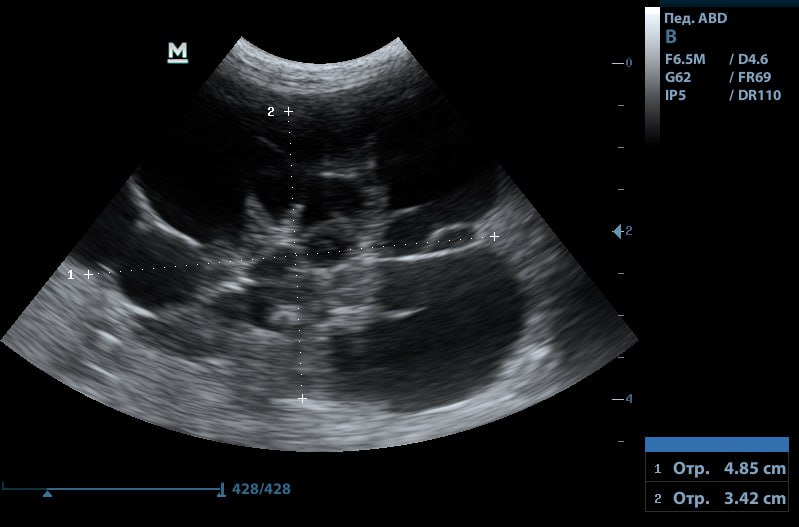

Данный диагноз ставят с помощью ультразвукового исследования. В случае поликистоза на УЗИ видно, что дифференциация слоев в почке сглажена или отсутствует. В ткани визуализируются множественные полости с жидким содержимым.

Снимок почки с поликистозом, черные включения — кисты

Если на УЗИ подтверждается поликистоз, ветеринарные врачи уже могут поставить животному диагноз «‎хроническая болезнь почек 1 стадии». В обязательном порядке исследуем кровь на биохимию, общий анализ крови и мочу на общий анализ и соотношение белок-креатинин.